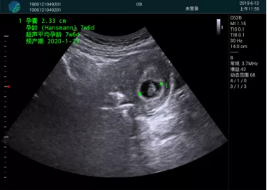

病例一:

清晰顯示孕囊,通過軟件包計算孕齡7w+6d

M20實時引導,術中清晰顯示孕囊被破壞和抽吸針的過程,清晰顯示吸引針

抽吸結束后縱切子宮,孕囊已被完全抽吸,未見明顯殘留

橫切子宮,發(fā)現右側宮腔靠近宮角處有少許脫模樣殘留

M20引導下,抽吸針找到右側宮角處再次清掃

二次抽吸后再次進行超聲檢查,宮腔未見殘留,宮腔線清晰顯示